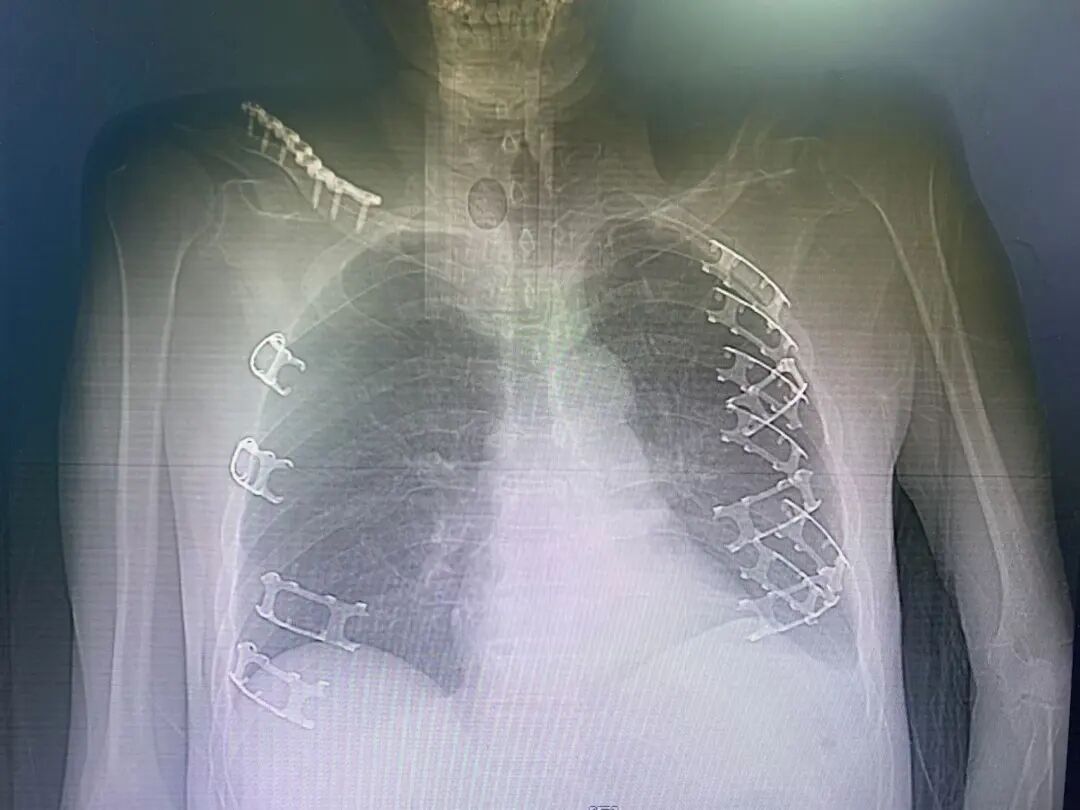

患者术后胸部X线片

图片